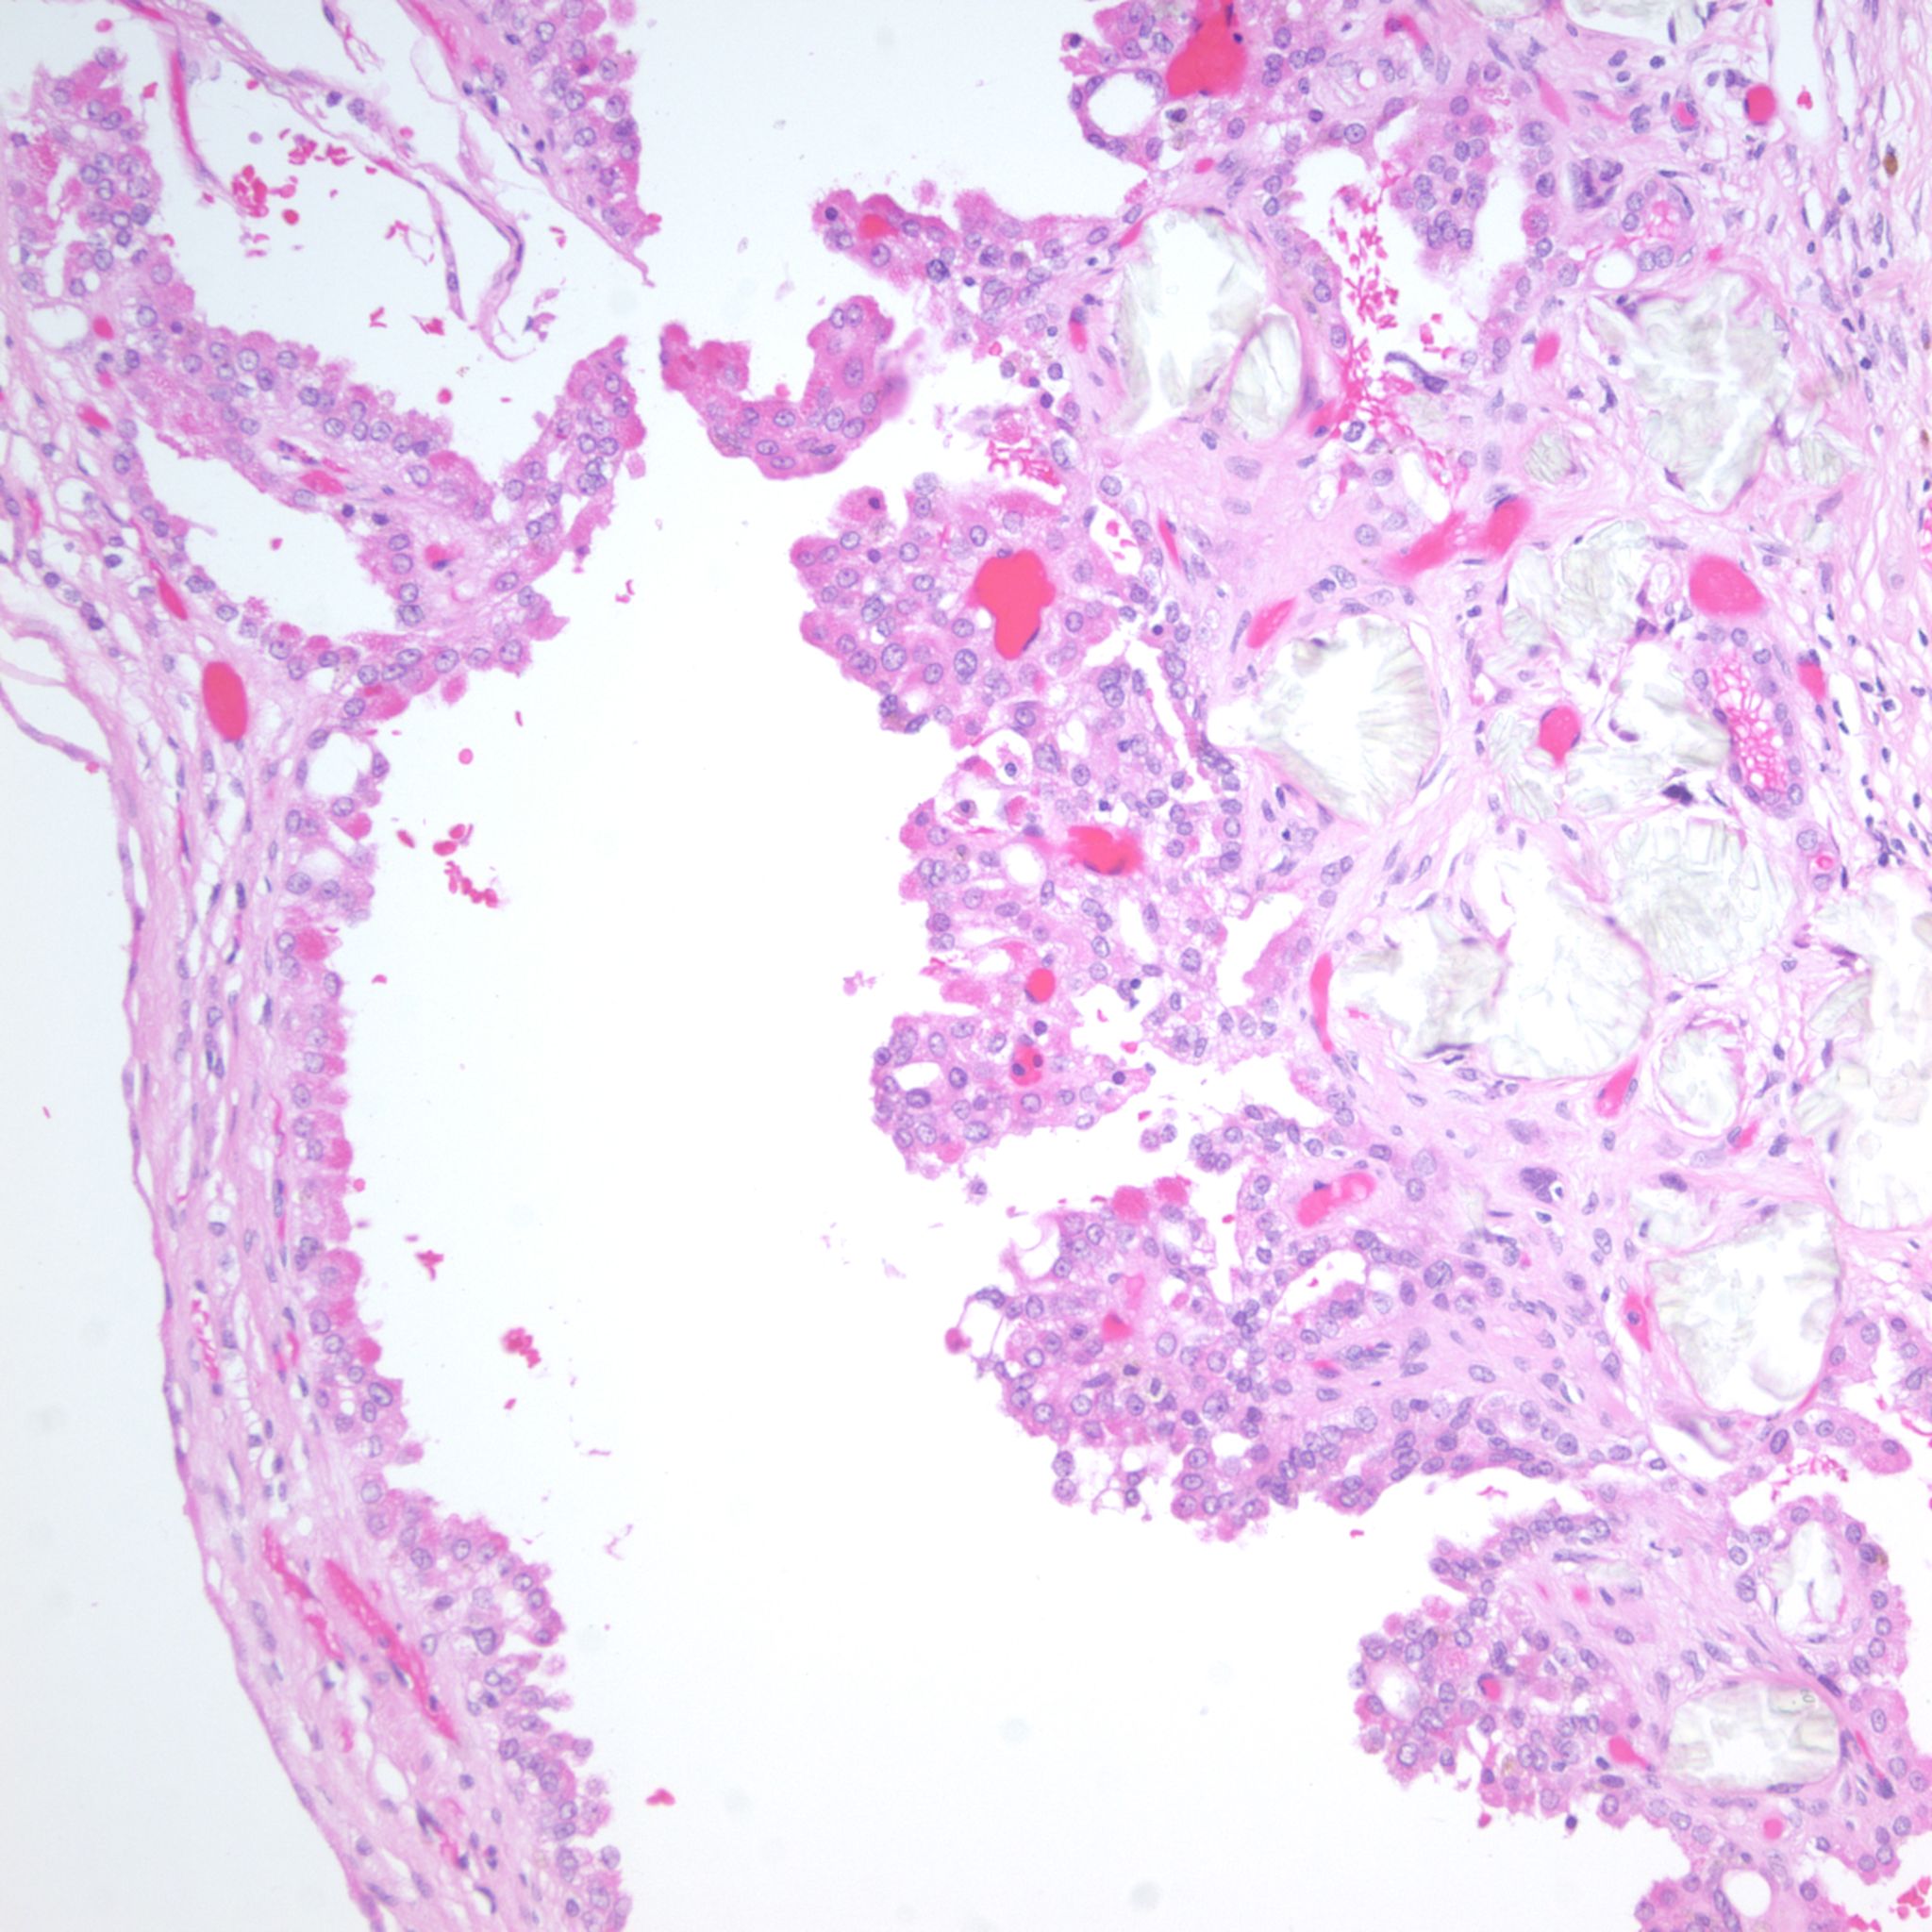

Classification of renal tumors

Case ID: 1237